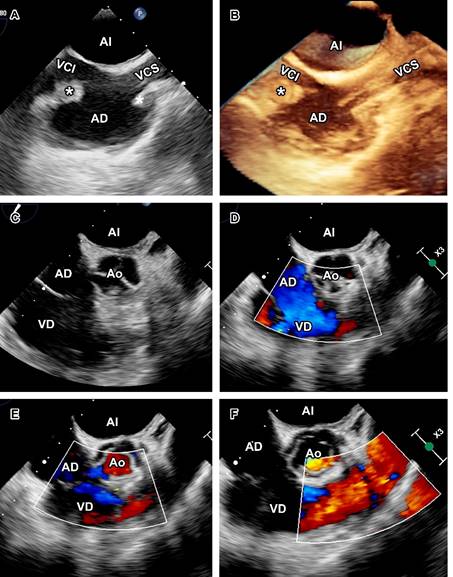

A la exploración física, ruidos cardiacos y respiratorios se auscultaron sin alteraciones. Laboratorios solo reportaron anemia (hemoglobina 8.7 g/dL). Ante sospecha de EI se tomaron hemocultivos y se inició tratamiento con vancomicina más ceftazidima. El ecocardiograma transtorácico (ECOTT) con mala ventana acústica mostró catéter de hemodiálisis engrosado con vegetación en la aurícula derecha (Figura 1), y se realizó ecocardiograma transesofágico (ECOTE), observándose vegetación en el catéter de hemodiálisis así como en aurícula derecha y sin compromiso valvular (Figura 2).

Figura 2: Ecocardiograma transesofágico: vista bicaval a 90° (A-B) con catéter de hemodiálisis en vena cava superior con vegetación filiforme 36 × 5 mm (*) y vegetación en aurícula derecha a nivel de desembocadura de vena cava inferior (*) de 26 × 14 mm. Vista eje corto a 45°, (C-F) sin vegetaciones ni afección valvular.